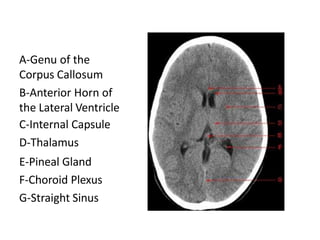

A-Genu of the

Corpus Callosum

B-Anterior Horn of

the Lateral Ventricle

C-Internal Capsule

D-Thalamus

E-Pineal Gland

F-Choroid Plexus

G-Straight Sinus

A-Genu of the CorpusCallosum B-Anterior Horn of the Lateral Ventricle C-Internal Capsule D-Thalamus E-Pineal Gland F-Choroid Plexus G-Straight Sinus